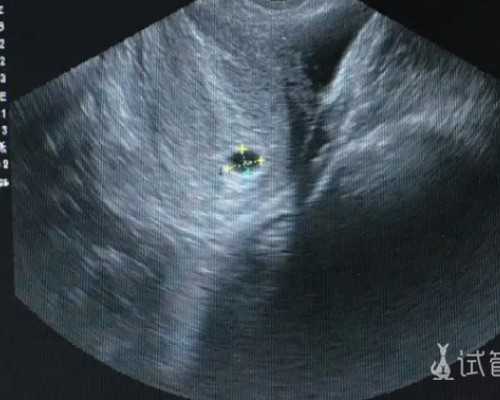

卵泡对于卵子而言是很重要的,如果监测出卵泡发育不良,应该如何治疗呢?

卵泡发育不良应该如何治疗

对于卵泡发育不良者,一般可采用促排卵药物,常用的西药为克罗米芬,也可运用绒毛膜等。但......